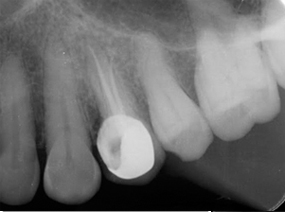

During root canal treatment dentist will remove the infected nerve tissue and bacteria to replace it with artificial material called gutta percha. followed by filling and crown on top of it to protect the tooth and serve you for a longer time.Why is this treatment needed?

(Notice broken tooth with (Both canals filled with gutta percha) cavity involving nerve)

(Root canal treatment completed with PFM crown)